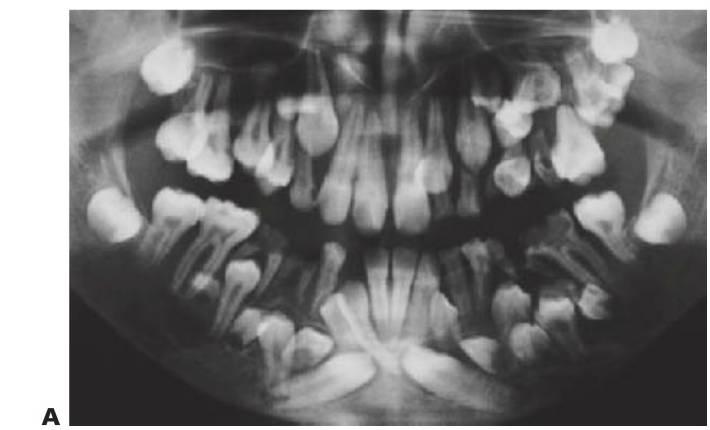

Hipodoncia, oligodoncia y anodoncia son los términos que designan los diferentes grados de progresión de la ausencia de dientes, si bien el término hipodoncia es el más utilizado debido a que se refiere a un número indeterminado de dientes ausentes (fig. 9.1 A). La oligodoncia designa la ausencia de seis dientes o más, y la anodoncia la ausencia completa de dientes. Todos estos casos se producen debido a un fallo en el desarrollo. El término «dientes ausentes congénitamente» no puede aplicarse a la dentición permanente, ya que estos dientes comienzan su desarrollo después del nacimiento, y tampoco a la dentición temporal ya que esa ausencia dental no puede determinarse de forma clínica en el momento de nacer; asimismo, el término «anodoncia parcial» carece de sentido. Sucede con frecuencia que los grados de hipodoncia aparezcan de manera esporádica o bien tengan un componente hereditario. Cuando a un individuo le faltan muchos dientes se debe estudiar a otros miembros de la familia afectados.

Displasias ectodérmicas

La displasia ectodérmica describe un grupo de trastornos del desarrollo que con frecuencia son heredados y afectan a las estructuras derivadas del ectodermo, como el pelo, los dien tes, las uñas, la piel y las glándulas sudoríparas. La forma más común es la forma hipohidrótica ligada al cromosoma X (OMIm305100, EDA1, Xq12-q13.1 [brazo corto del cromosoma X]). En este trastorno, la presentación usual es la de un niño varón con:

- Varios dientes ausentes (fig. 9.1 B).

- Cabello fino y ralo (fig. 9.2A, B).

- Piel seca (fig. 9.2A).

- Hipoplasia maxilar.

- Eversión de los labios.

- Pigmentación alrededor de la boca y los ojos.

Los dientes son pequeños y cónicos y a menudo presentan un gran diastema anterior (fig. 9.3). Sus manifestaciones pueden limitarse a un solo diente ausente o a un incisivo lateral en clavija (v. hipótesis de Lyon, más adelante) y las mujeres heterocigóticas suelen ser diagnosticadas gracias a este tipo de dentición.

Dentro del grupo de displasias ectodérmicas, se observan asimismo modos de herencia autosómica tanto dominante como recesiva. Si se compara con la displasia ectodérmica hipohidrótica ligada al cromosoma X, en las familias con este trastorno no existen diferencias tan acentuadas en cuanto al grado de trastorno entre los hombres y las mujeres (figs. 9.2A, 9.4). Se han identificado mutaciones en el gen MSX1 (4p16.1) en familias con terceros molares y segundos premolares ausentes con o sin paladar hendido/labio leporino, así como en familias con el síndrome diente-uña (Witkop). Se han observado mutaciones del gen PAX9 (14q12-q13) en otras familias con dientes ausentes de forma autosómica dominante.

El tratamiento dental de los niños afectados (que incluye la prevención, la ortodoncia y la prótesis) está cubierto por programas gubernamentales en algunos países.

Tratamiento

El objetivo del tratamiento es proporcionar una función adecuada, mantener la dimensión vertical y restaurar el aspecto estético. La mejor opción desde el punto de vista de las consideraciones sociales es el inicio del tratamiento a los 2-3 años de edad. Sucede a menudo que los padres pretendan con ahínco «normalizar» el aspecto del niño. Un primer paso suele ser la colocación de restauraciones de composite para enmascarar el aspecto «similar a un colmillo» del diente anterior caniniforme (fig. 9.3A). Más adelante se efectuará la provisión de prótesis para que sufra menos burlas, sobre todo en el momento en que el niño empieza a ir a la escuela. La prótesis puede prepararse tan pronto como al niño se le puedan tomar impresiones, pero la realidad es que el primer juego de prótesis suele llevarse en el bolsillo y a medida que el niño crece se desarrolla el deseo de tener un aspecto más normal. Gracias a una incentivación y refuerzo positivo del niño, la mayoría de los niños llevarán puestas sus prótesis.